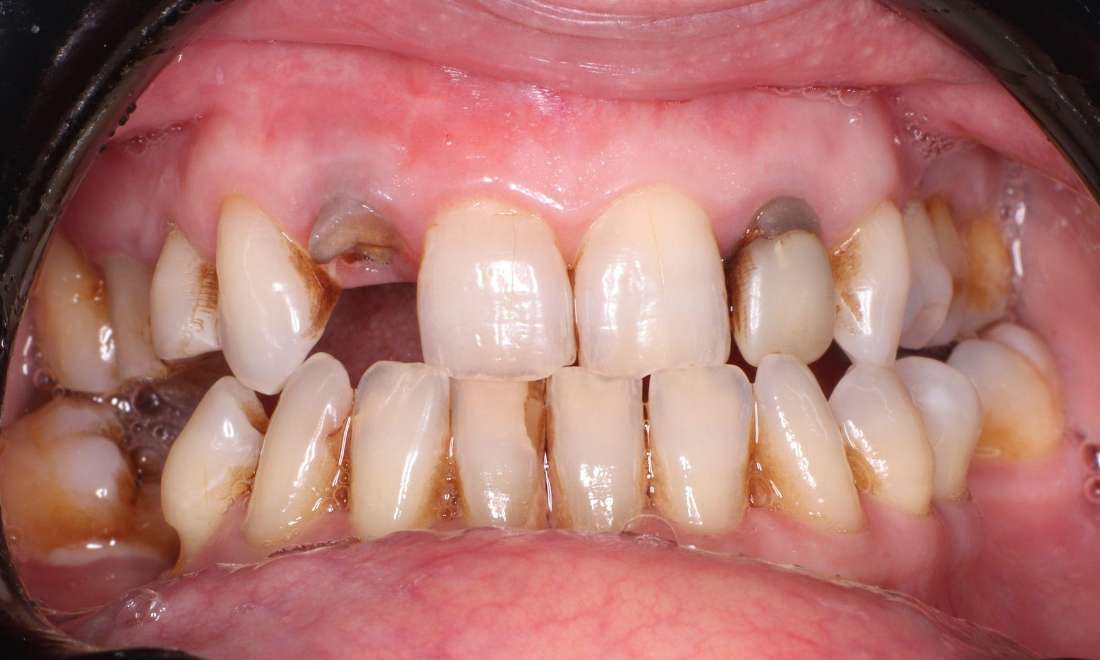

One of our patients came to us with a missing tooth and reported feeling self-conscious about their smile. We recommended a dental bridge to restore both function and aesthetics. Anchored to the surrounding teeth, the bridge provided a strong, reliable and natural-looking solution. After treatment, they could smile confidently and enjoy their favourite foods without discomfort.